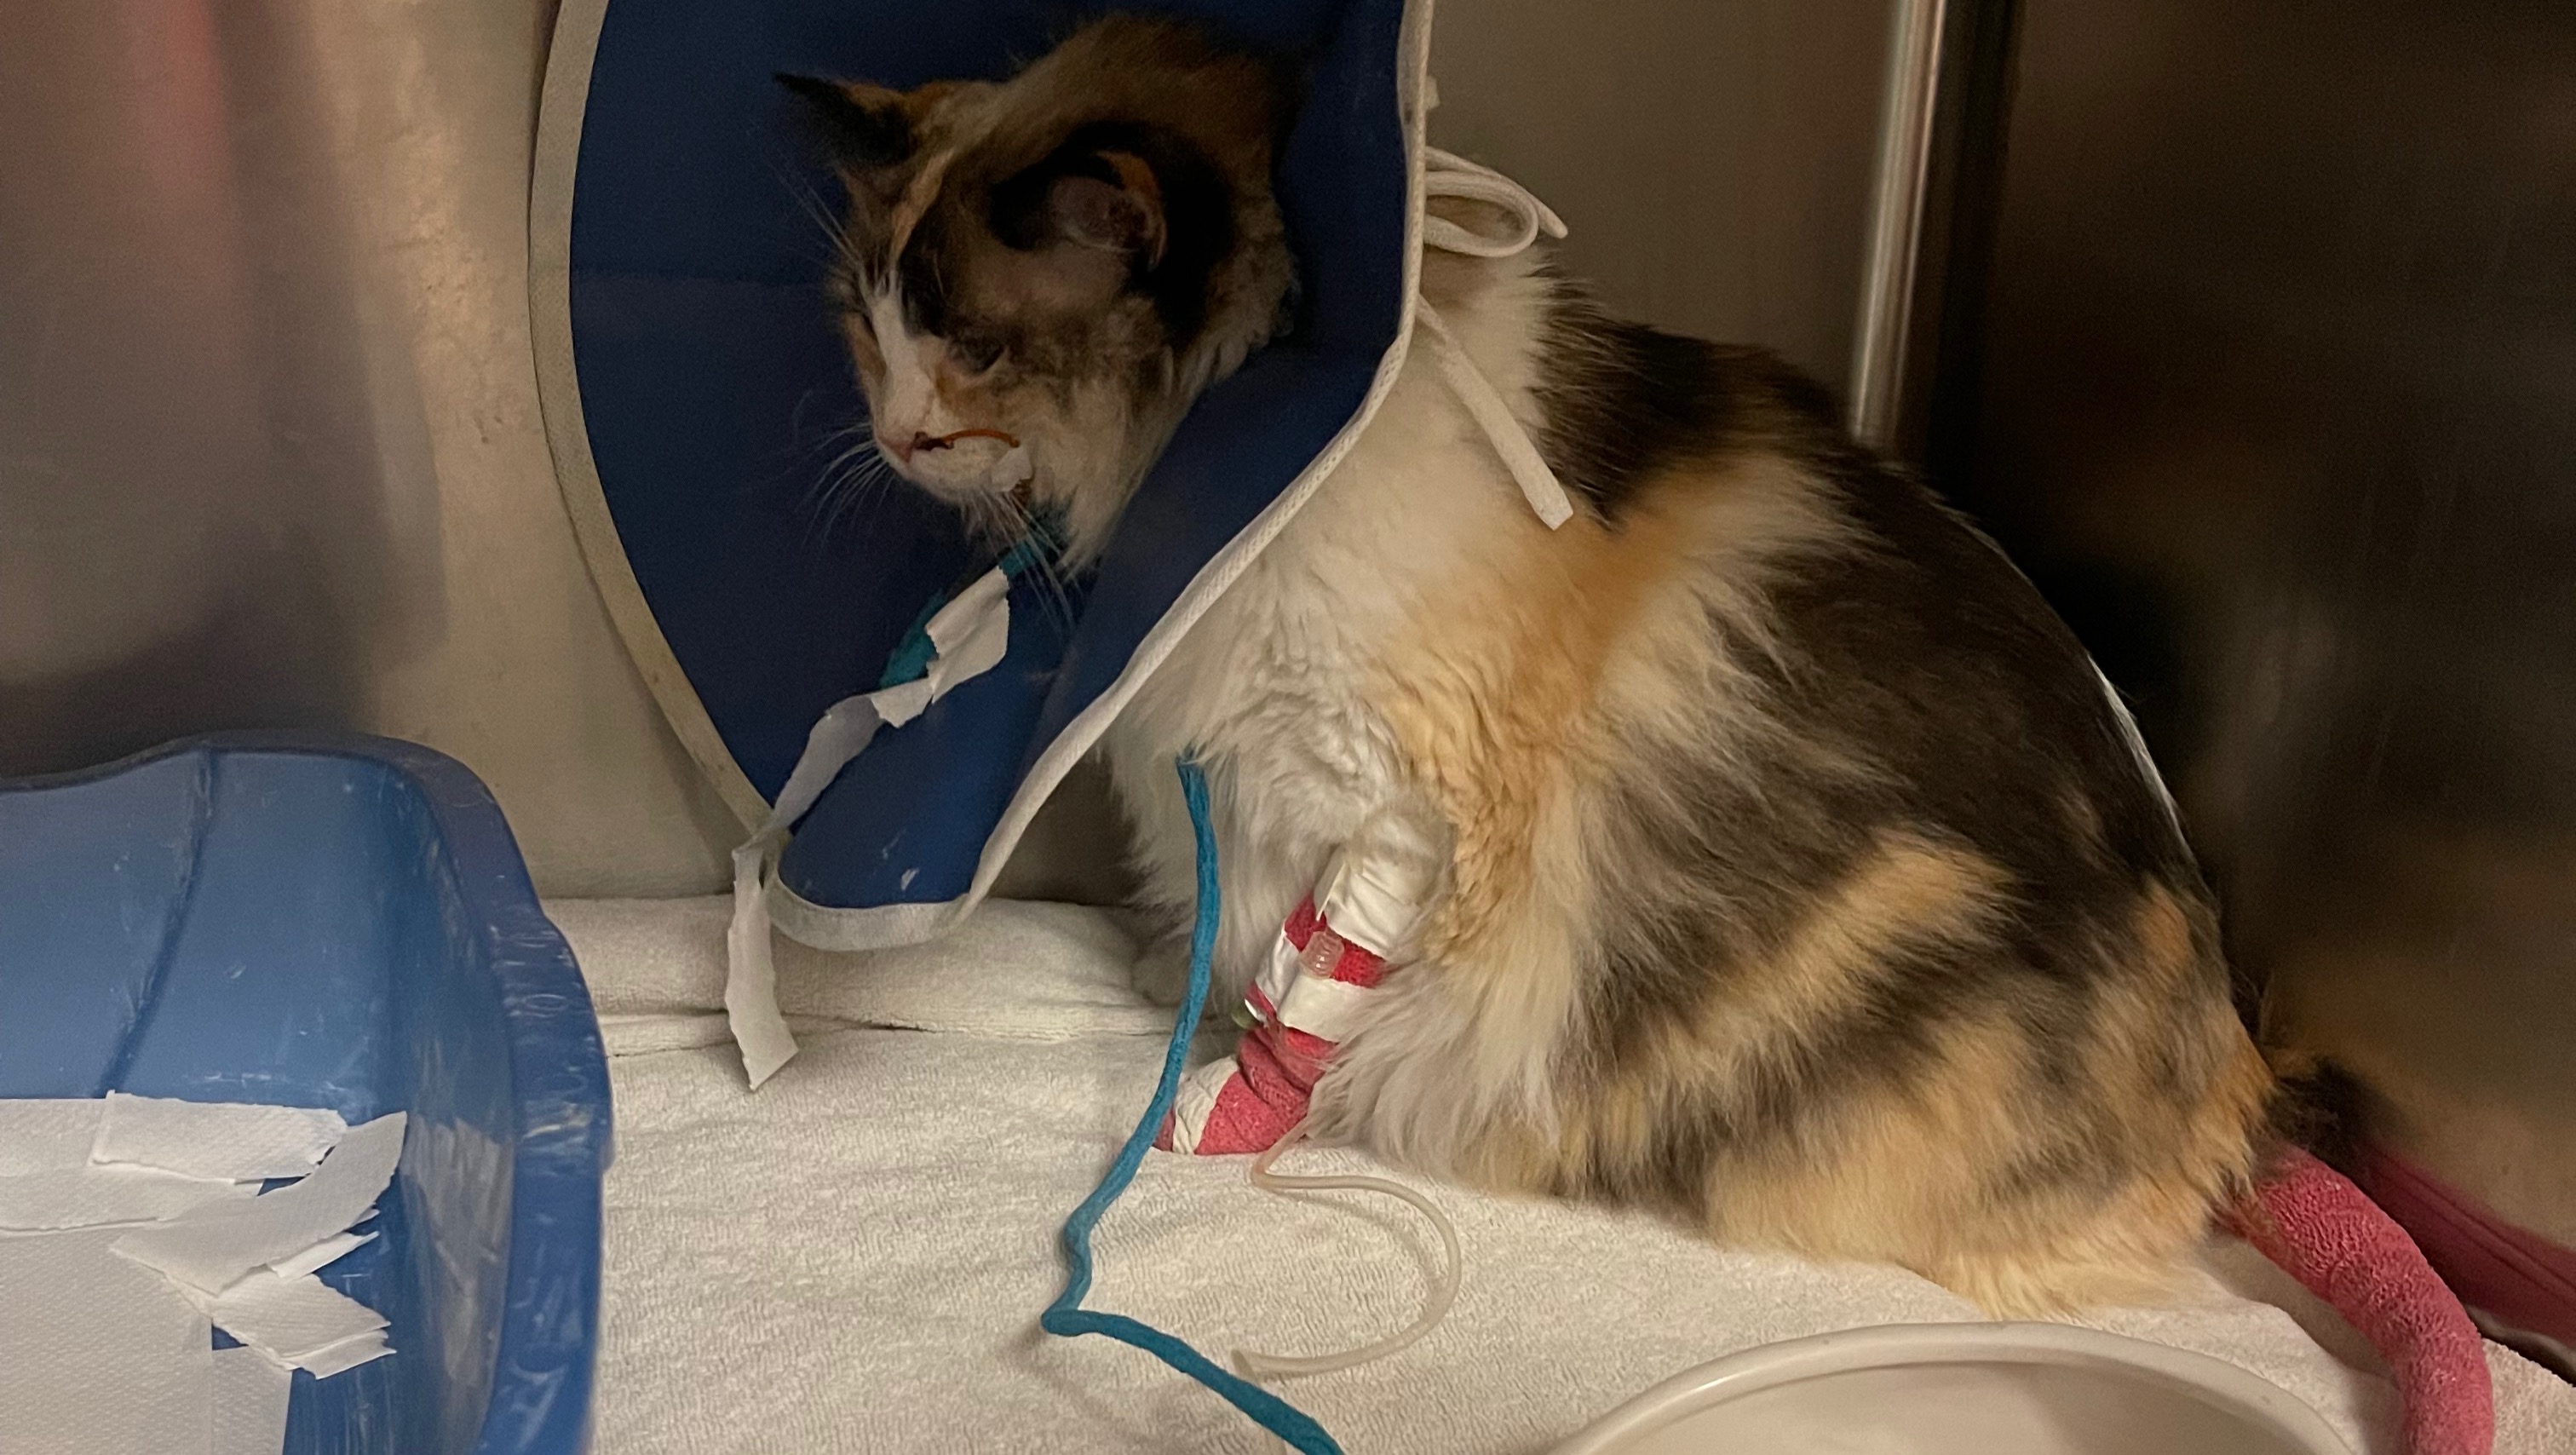

My sweet sweet Luna Bean developed severe constipation which turned into a massive bowel obstruction (see photos). She's been in the ICU at the vet hospital since Friday 9/24 receiving continuous fluids, bowel prep through NG tubes, endless enemas, meds and more. Poor thing is still obstructed and has been vomiting due to how backed up she is; I'm just hoping it doesn't come down to surgery. Since Friday I have now maxed 3 credit cards. I could really use some additional help paying a portion of these vet bills as I don't anticipate bringing her home yet.

See the zoomed in photos of the two bags...if anything comes from this, I hope it's that the company changes the appearance of these two bags, especially if "this happens all the time." This was a medication error which negatively impacted my poor kitty and has left me with >10k of debt.

Photos of my fluffy Ragdoll gal

Luna is such a sweet gentle cat with the most beautiful purr, thick coat, and stunning icy blue eyes. When she's home, we play tag and hide and seek (for real), she leaves tuffs of hair everywhere, and is constantly sleeping on her back next to me on the couch. The house is truly gloomy without her there...